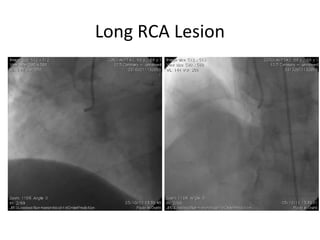

Long RCA Lesion